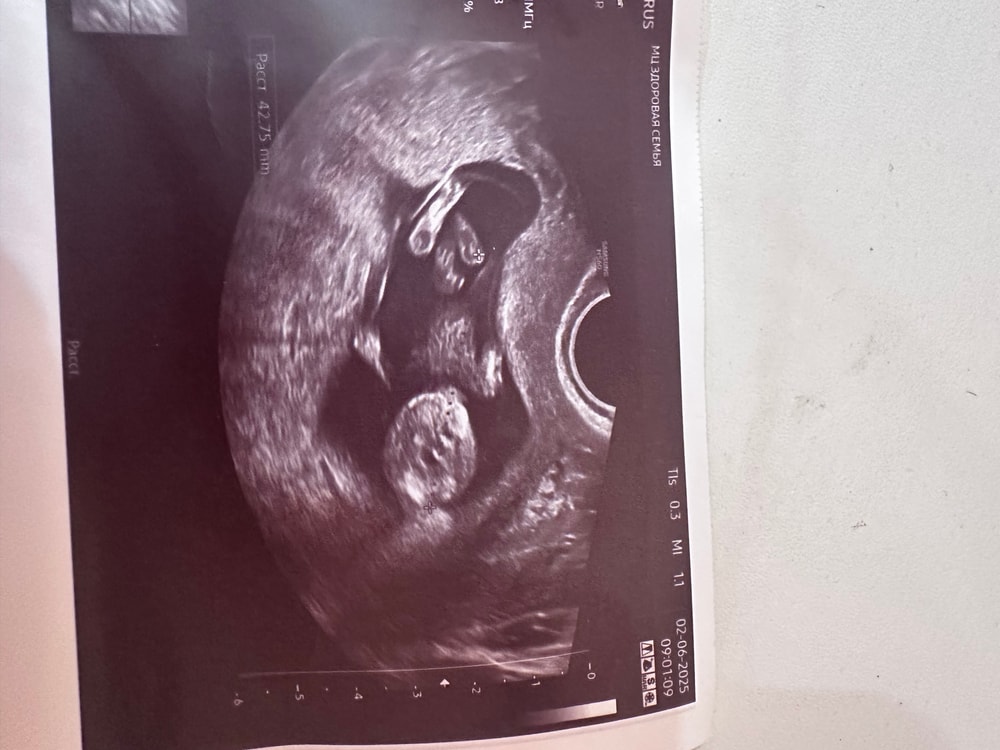

Aisha, меня тоже. Я ей этот вопрос задала дважды, она уверяет, что так нужно , чтобы лучше все рассмотреть , но я вам для примера сейчас покажу , как она КТР померила , думаю вы поймете почему у меня сомнения ) Изображение

Беременность, второй скрининг Наш первый скрининг